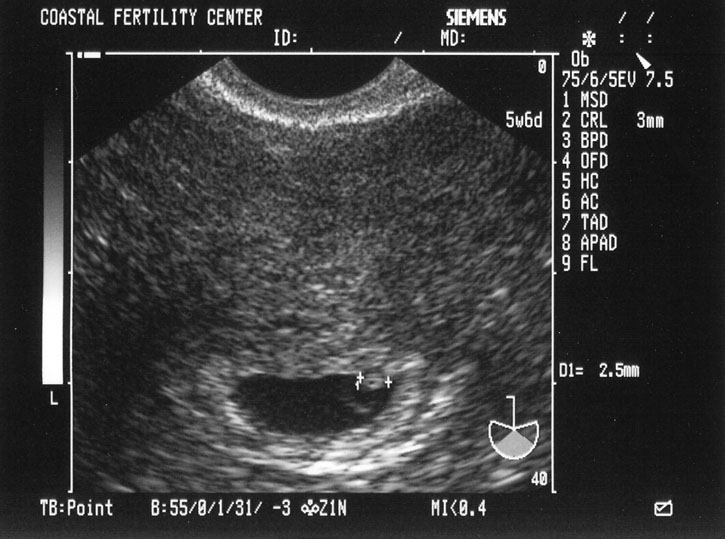

4/26/05 Baby B - 5w6d